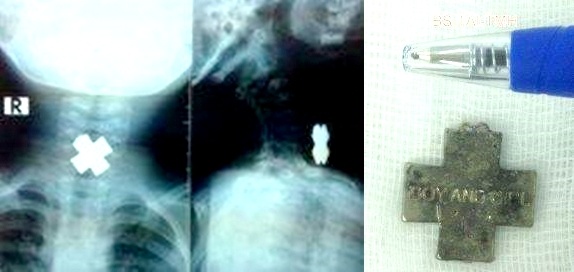

Kết quả X-quang cho thấy dị vật mắc trong cổ bé rất to, hình chữ thập nằm chiếm hết lòng thực quản. Các bác sĩ nhận định khả năng dị vật gây trầy, rách thực quản rất cao.

| Mặt dây chuyền hình chữ thập chắn ngang thực quản bệnh nhi. Ảnh: BV Nhi Đồng. |

Đội ngũ y tế quyết định tiến hành gây mê, dùng thủ thuật gắp dị vật ra khỏi thực quản cho bệnh nhi. Kết quả kiểm tra cuối cho thấy lòng thực quản của bé An chỉ tổn thương nhẹ niêm mạc, có thể nhanh chóng bình phục.